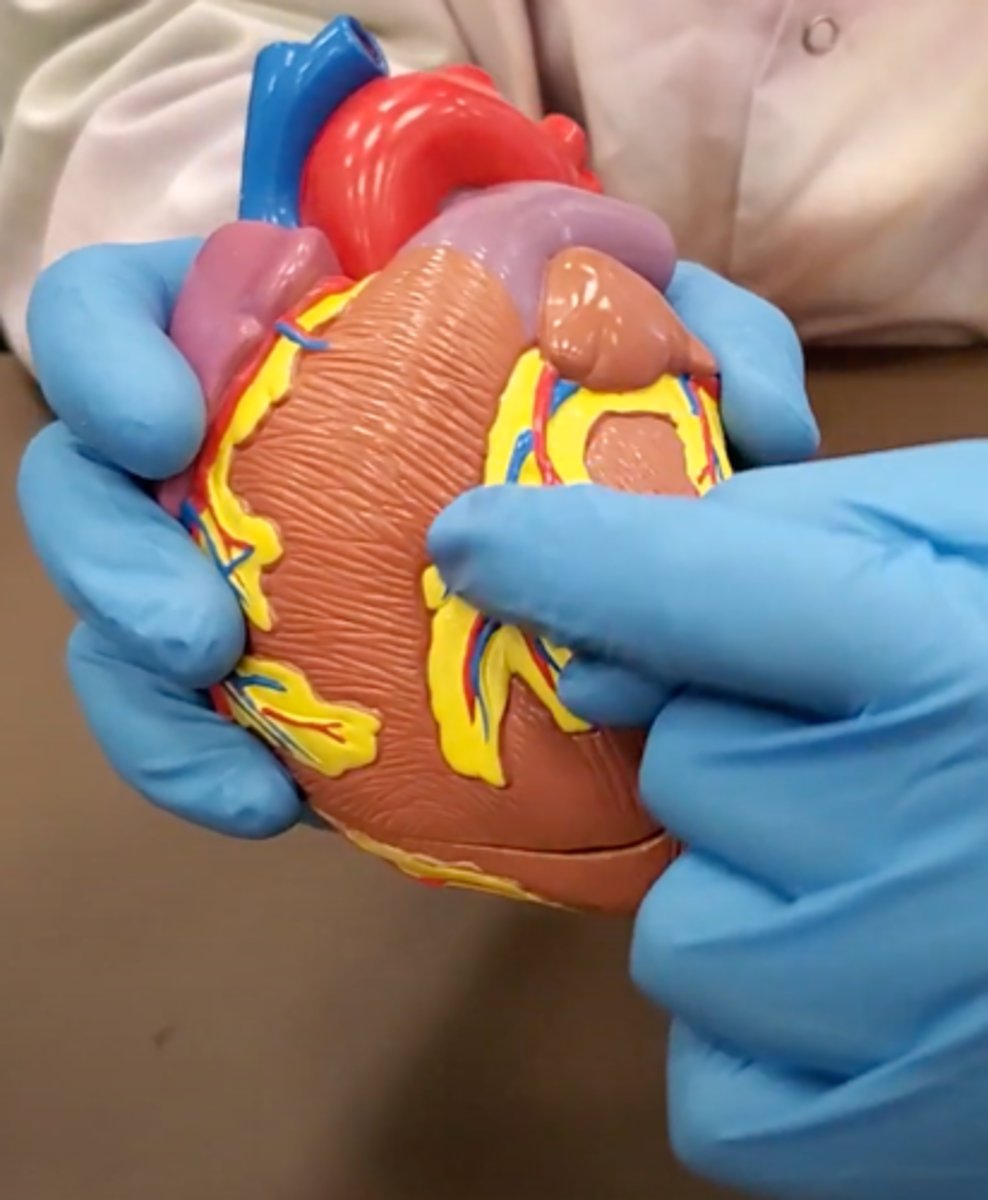

yellow sash of fat that tells you this if the front side of the heart (dissection)

pulmonary trunk (dissection)

t-shaped ribbon of fat on back side of heart (dissection)

left auricle (dissection)

right auricle (dissection)

left ventricle (dissection)

right ventricle (dissection)

right atrium (dissection)

left atrium (dissection)

bicuspid valve (dissection)

tricuspid valve (dissection)

aortic semilunar valve (dissection)

located between the left ventricle and the aorta

chordae tendineae (dissection)

thin bands of fibrous tissue that attach to the valves in the heart and prevent them from inverting